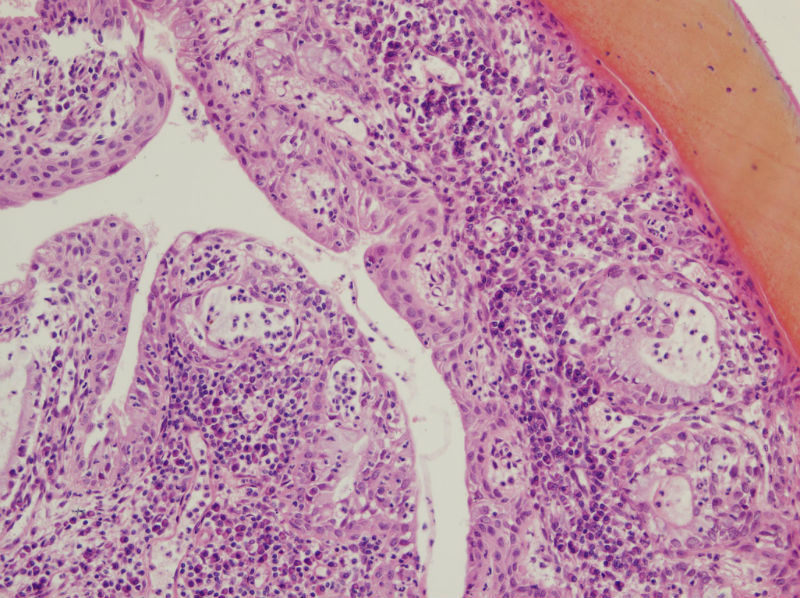

45岁,宫颈息肉?请老师指教

图3

我想请问,息肉的分型.另外患者服用大量妇科中成药物和腺体的鳞化有关吗?